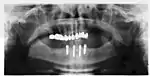

Panorex radiograph showing implants

Xray of four Straumann implants and abutments

When a removable denture is worn, retainers to hold the denture in place can be either custom made or "off-the-shelf" (stock) abutments. When custom retainers are used, four or more implant fixtures are placed and an impression of the implants is taken and a dental lab creates a custom metal bar with attachments to hold the denture in place. Significant retention can be created with multiple attachments and the use of semi-precision attachments (such as a small diameter pin that pushes through the denture and into the bar) which allows for little or no movement in the denture, but it remains removable.[17]:33–34 However, the same four implants angled in such a way to distribute occlusal forces may be able to safely hold a fixed denture in place with comparable costs and number of procedures giving the denture wearer a fixed solution.[54]